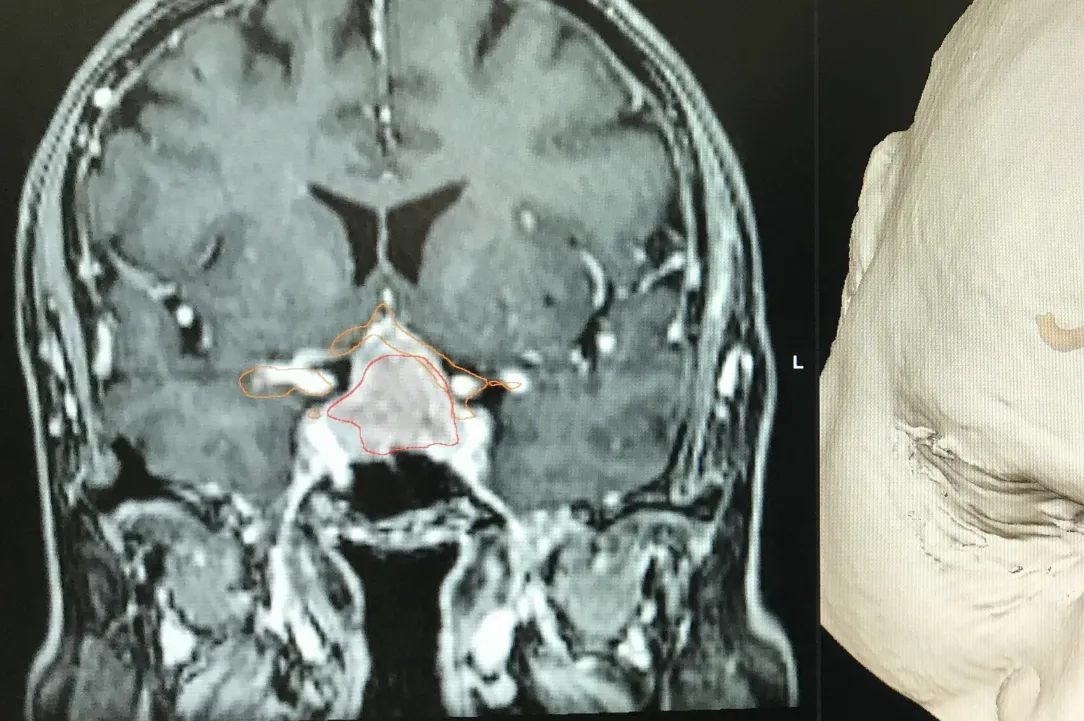

Les adénomes hypophysaires sont majoritairement des tumeurs bégnines qui se développent à partir de la glande hypophysaire.

On peut les catégoriser par leur activité et par leur volume. En effet, ceux-ci peuvent secréter de manière excessive des hormones hypophysaires ou peuvent, par leur volume, comprimer les structures fonctionnelles et, en particulier, le nerf optique et le chiasma.

Les adénomes non-secrétants sont souvent découverts soit de manière fortuite lors d’une imagerie cérébrale, soit en lien avec leur volume excessif. On parle alors de macroadénomes qui sont responsables de troubles le plus souvent visuels par compression du nerf optique et ou du chiasma. Leur traitement est chirurgical s’ils sont symptomatiques. L’acte chirurgical consiste à l’exérèse de la tumeur via les cavités nasales et le sinus sphénoïdale (voie transnasale, transphénoïdale). L’abord peut se faire sous endoscope ou microscope. La tendance actuelle est d’utiliser la voie endoscopique en étroite collaboration avec l’équipe d’ORL. Dans certaines situations, un traitement combinant l’exérèse chirurgicale et un traitement par radiochirurgie peut être discuté en concertation oncologique multidisciplinaire. Vous retrouverez au sein de notre service de Neurochirurgie du CHIREC, l’ensemble de ces collaborations possibles.